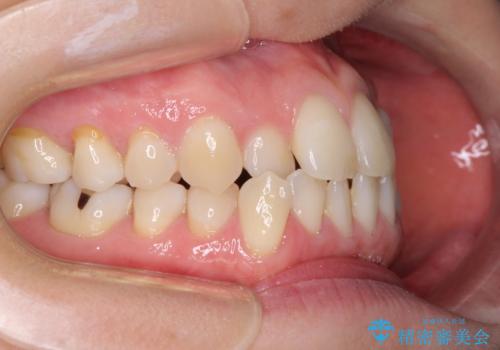

- 受け口傾向でクロスバイトの前歯を治したいとのことで来院された患者様です。

下顎骨が若干左側に変位していたため、右側にアンカースクリューを使用し、積極的に移動させながらインビザラインにて矯正治療を行うこととしました。